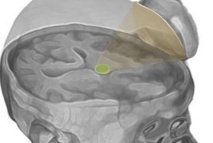

Ilustración de los ultrasonidos dirigidos hacia el tálamo (en verde). Imagen: Martin Monti. Fuente: UCLA.

La técnica utiliza más concretamente la estimulación sónica para excitar las neuronas del tálamo, una estructura que sirve como eje central del cerebro para el procesamiento de la información.

El dispositivo, del tamaño de un platillo de taza de café, genera una pequeña esfera de energía acústica que puede ser dirigida a diferentes regiones del cerebro para excitar el tejido cerebral.

La técnica utiliza más concretamente la estimulación sónica para excitar las neuronas del tálamo, una estructura que sirve como eje central del cerebro para el procesamiento de la información.

El dispositivo, del tamaño de un platillo de taza de café, genera una pequeña esfera de energía acústica que puede ser dirigida a diferentes regiones del cerebro para excitar el tejido cerebral.

Esta técnica se dirige al tálamo porque, en personas cuya función mental está profundamente alterada después de una coma, el rendimiento de esta región cerebral está típicamente disminuido. Normalmente, los medicamentos que se prescriben en estos casos se dirigen al tálamo de manera indirecta.

Esta técnica se dirige al tálamo porque, en personas cuya función mental está profundamente alterada después de una coma, el rendimiento de esta región cerebral está típicamente disminuido. Normalmente, los medicamentos que se prescriben en estos casos se dirigen al tálamo de manera indirecta.